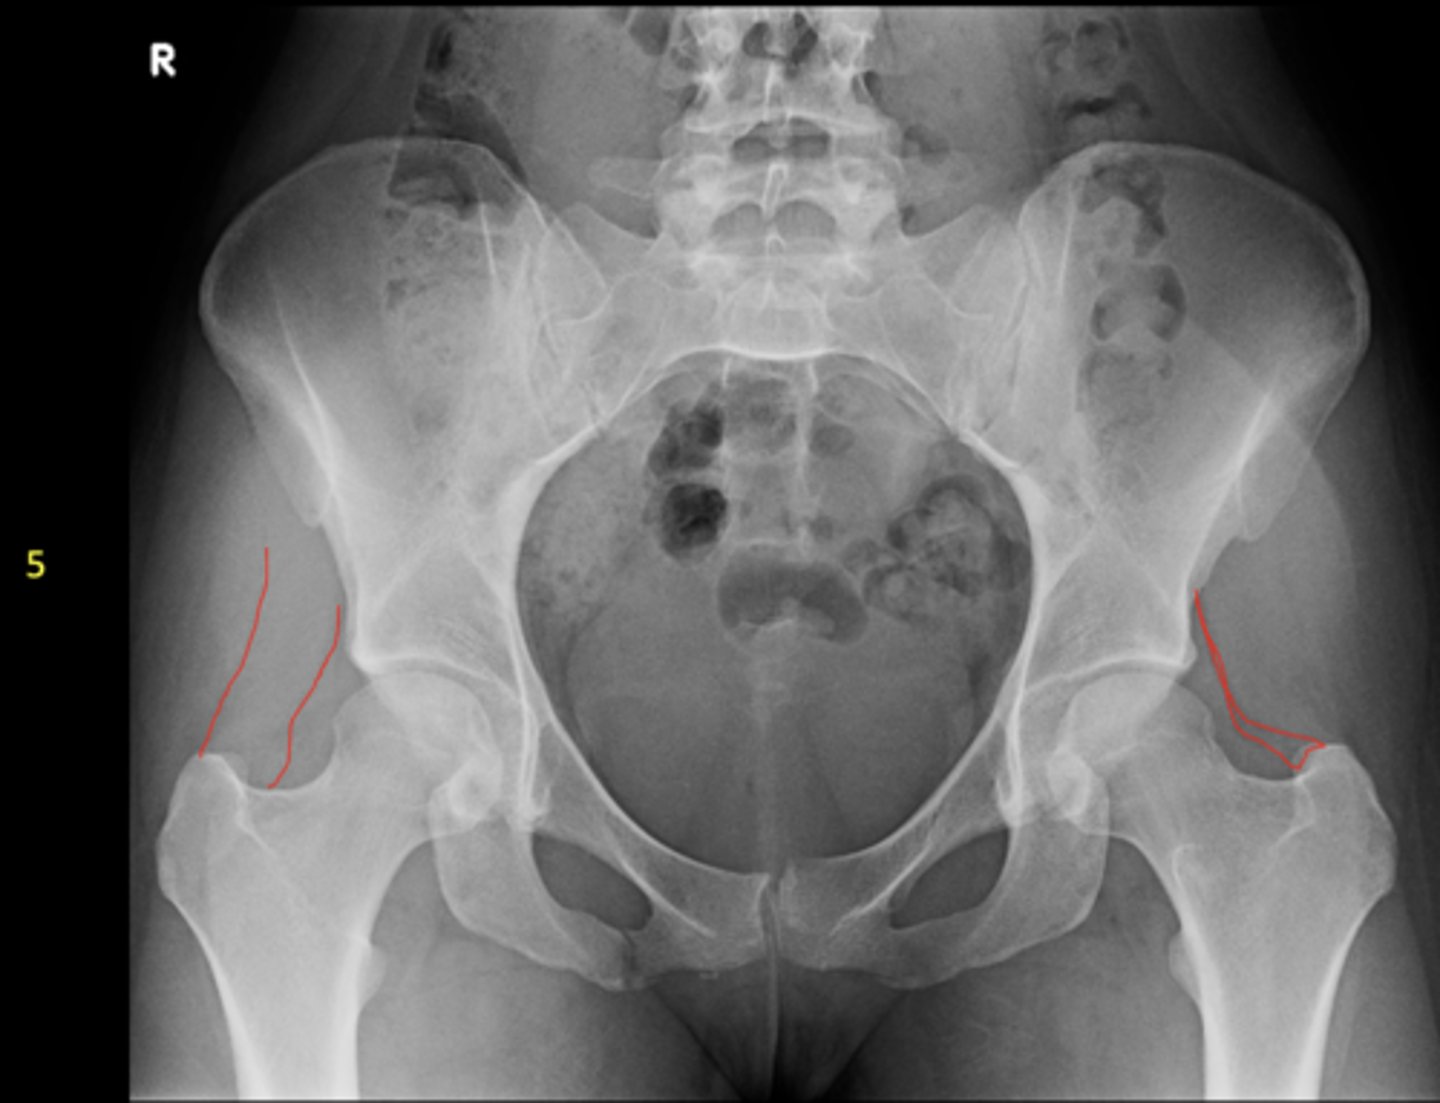

Shenton's line

ID measurement

- AP hip

- AP pelvis

- Smooth arc along femoral neck

- Obturator foramen

Shenton's line landmarks

Continuous and smooth

Shenton's line normal measurements

- Hip dislocation

- Femoral neck fracture

- Slipped epiphysis

Clinical significance of Shenton's line

<p>Clinical significance of Shenton's line</p>